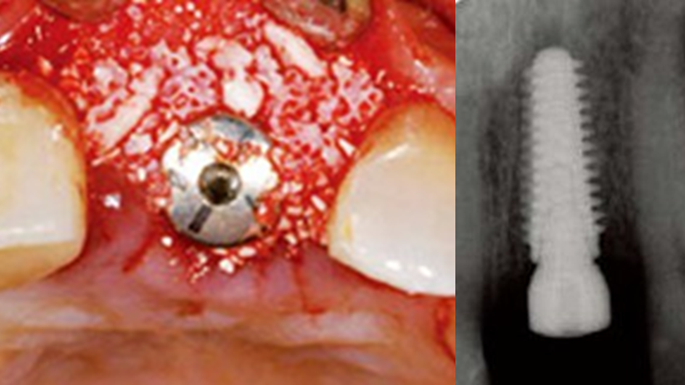

Clinical case: Immediate post-extraction insertion of implant & immediate loading

- Courtesy of Prof. Giuseppe Luongo, Italy -

AnyRidge, immediate loading, single implant, multicenter study, maxillary anterior, Prof. Giuseppe Luongo, single replacement

AnyRidge implant system

Immediate functional loading of single implants: a multicenter study with 4 years of follow-up

/J Dent Res Dent Clin Dent Prospect 2018; 12(1):26-37 | doi: 10.15171/joddd.2018.005

https://www.ncbi.nlm.nih.gov/pubmed/29732018